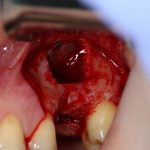

Вот клиническая картина через 4 месяца после ранее проведенной имплантации с остеопластикой:

Как видишь, коллеги из недалекой дружественной страны не осилили снятие швов. Мне это не нравится, хотя и объясняет, почему люди готовы ехать за тыщи километров ради 20-минутной операции удаления зуба мудрости.

Ну хорошо. Швы сняли. Делаем разрез. Обрати внимание, что после всех проведенных операций у нас остается очень небольшой по ширине слой жевательной слизистой оболочки: